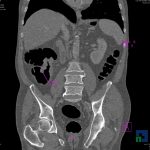

- Diagnosticul fracturilor:

- Unice

- Multiple

- Cu înfundare

- Complexe cranio-sinusale

- Complexe cranio-etmoidale

- Complexe cranio-orbitare

- Complexe cranio-faciale